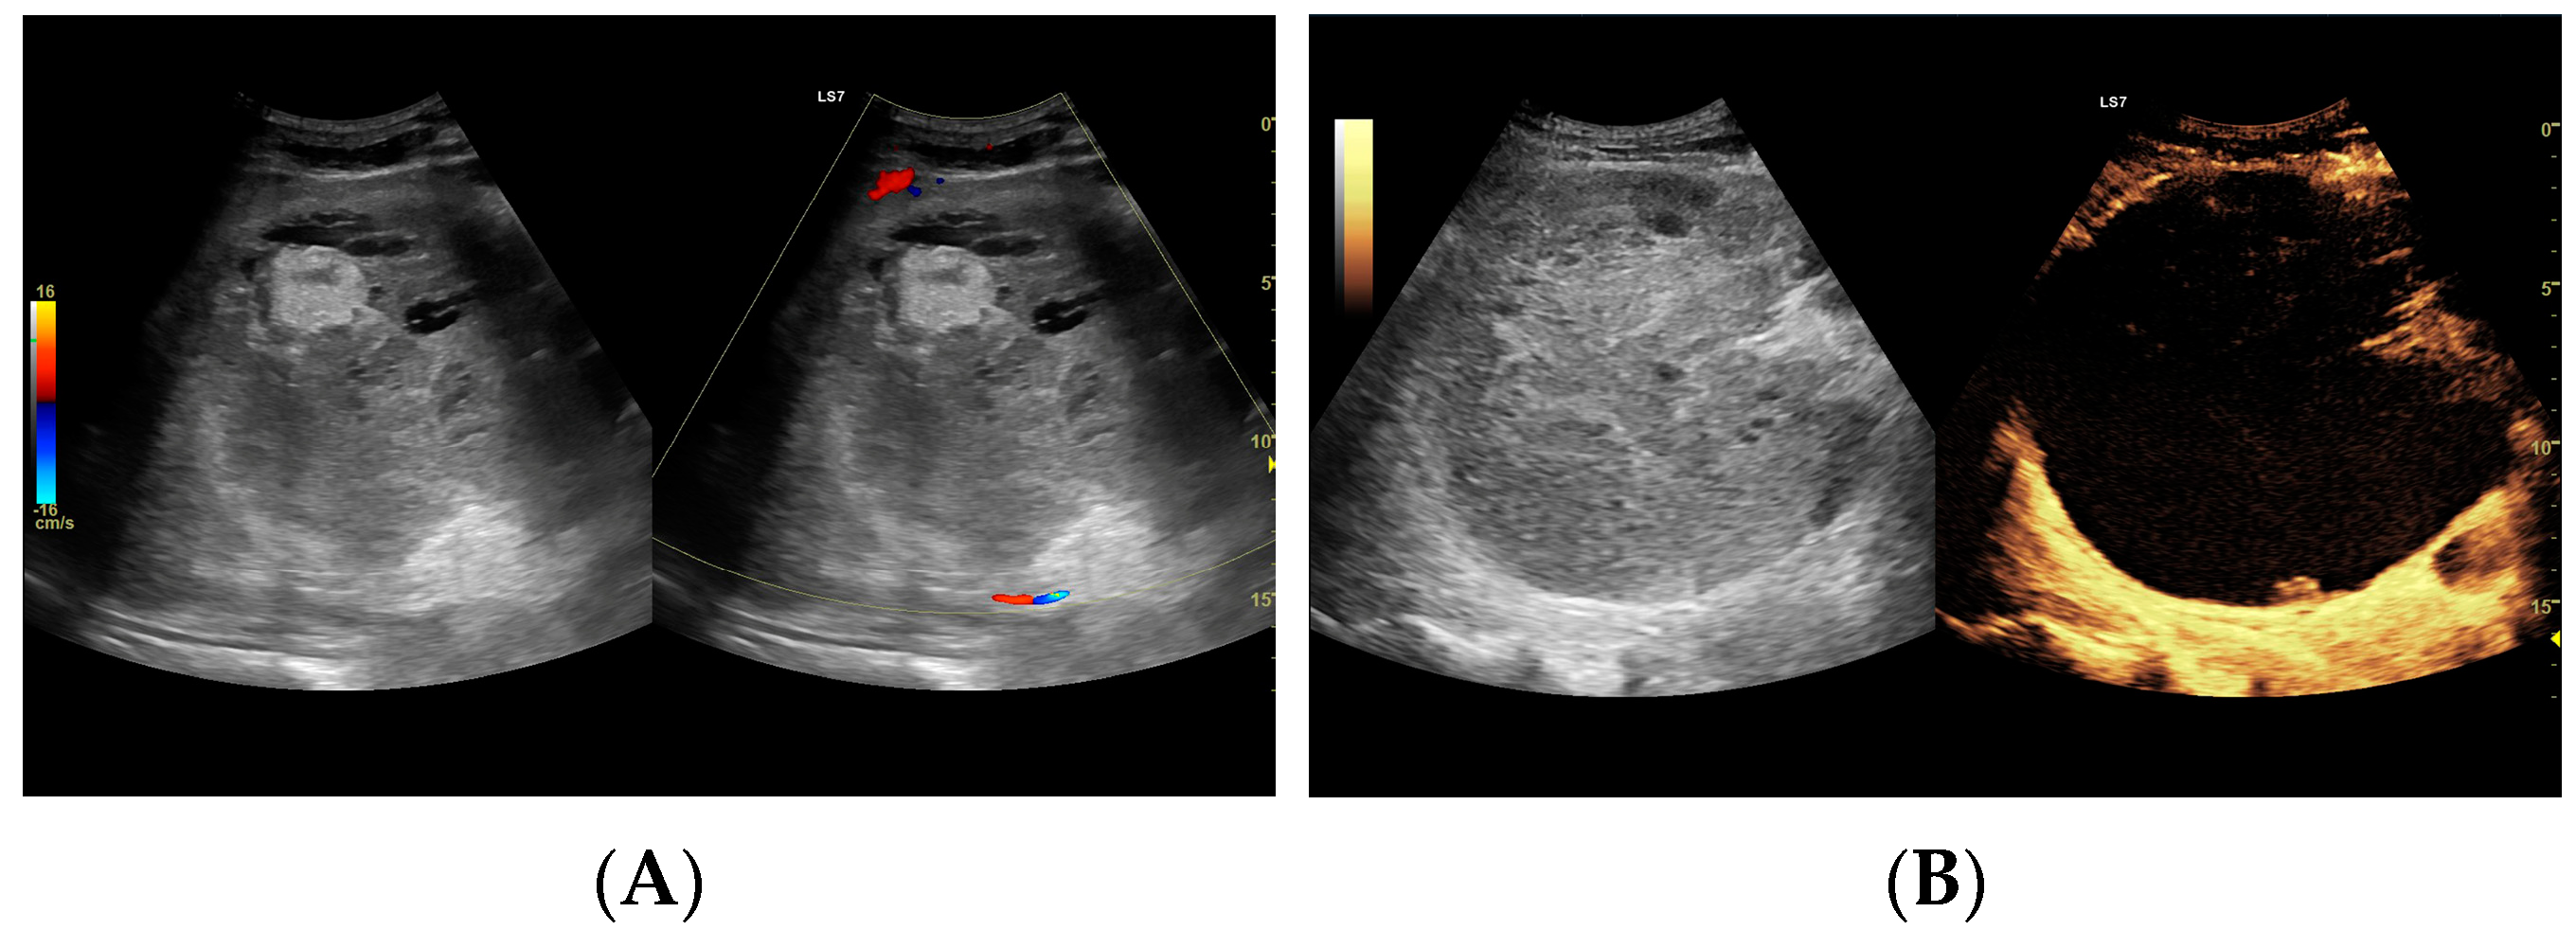

3.2.1. Arterial Phase

3.2.2. Early Venous Phase

3.2.3. Late Venous Phase